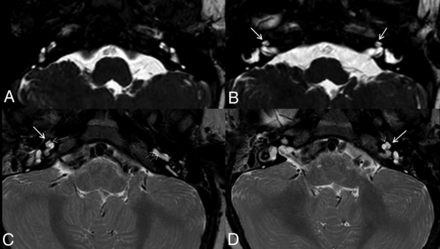

3D volume-rendering of the CH4 AOUT in patient 2 with a WWS phenotype and POMT1 variant (A) in comparison with a healthy control (B). Note the marked cochlear hypoplasia in A (arrow) in comparison with normal 2½ cochlear turns in B. The vestibule and lateral semicircular canals are normal in both patients.

This morphology was found in 13/24 patients. Most interestingly, the pronounced CH4 with an anterior offset of the upper turn (CH4 AOUT) was present in 12/13 of patients with WWS but only 1/11 of the remaining phenotypes, a patient with MEB. The remaining patient with WWS also had a small cochlea with a normal basal turn (CH4)6,12 but with better developed upper turns, similar to the other less severe CH4 found in some of the patients with MEB and FCMD (Fig 3). Among the MEB phenotypes, 5/8 patients had normal cochleae, 1/8 had CH4 AOUT, and 2/8 showed a less severe form of CH4. Patients with FCMD had normal cochleae in 2/3 cases, while 1 subject had a less severe form of CH4. In all patients, we found that the vestibules and semicircular canals were normal (Fig 2). The vestibulocochlear nerves were bilaterally present in all cases (on axial T2 images).